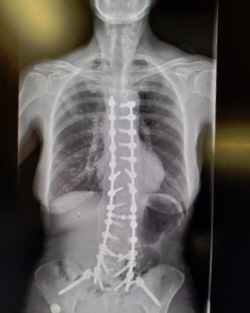

The x-rays for the 5 year checkup show that everything is holding just fine. I was ready to have them make sure that the rods and screws were still doing okay. Remember those of us that have had this much surgery, find that doctors, family and people around us have a hard time remembering that we cannot do what others can. I carry my pictures of the x-rays in my phone.

Here are my January 2022 x-rays